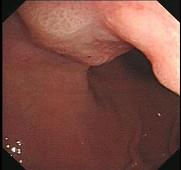

问题 男性54岁,间歇性上腹部不适4年,餐后加重,嗳气来诊。胃镜检查如图,应采取下列哪种治疗方法为宜 ( )

选项 A.西咪替丁 B.吗丁啉 C.吗丁啉+法莫替丁 D.洛赛克 E.手术治疗

答案 E